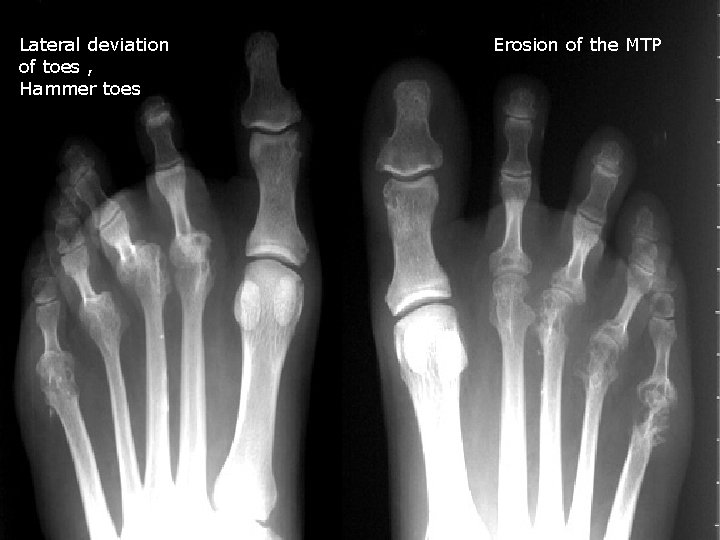

Lateral deviation of toes , Hammer toes Erosion of the MTP